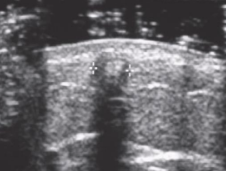

Chronic phase of foreign body

Foreign body present > 10 days

Dense granular material develops around FB

Inflammatory response → clean shadowing similar to bone